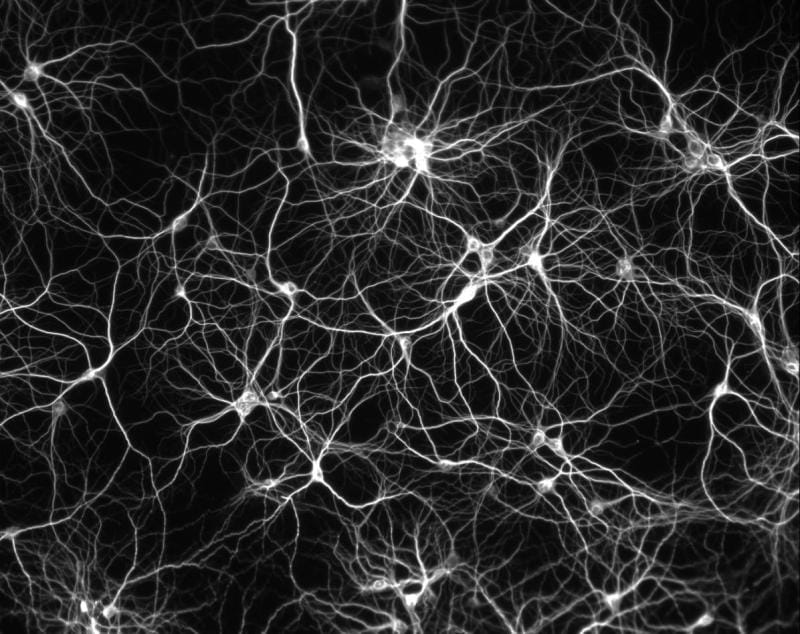

Neuronas/Neurons

Las neuronas son células especializadas en detectar sucesos y memorizarlos para construir conocimiento, capacidad anticipativa. Son individuos sensibles, con pasado, presente y futuro fundidos en su membrana.

Las neuronas imaginan la realidad, la sueñan a todas horas y toman decisiones que nos protegen de lo que han aprendido a temer.

Las neuronas de todos los bichos vivientes son iguales. Los sapiens (ma non troppo) no tenemos ningún tipo de neurona en exclusiva. Simplemente disponemos de más densidad de conexiones. De ese modo podemos imaginar más que otras especies. No estamos atados a lo que ha sucedido. Soñamos.

Neurons are cells specialized in detecting events and memorizing them in order to build knowledge, anticipative capacity. They are sensitive individuals with a past, a present and a future mixed in their membrane.

Neurons imagine the reality, they dream about it at all times and make decisions that protect us from what they have learned to fear.

Neurons of all living creatures are equal. Sapiens (ma non troppo) do not have any kind of exclusive neuron. We just have a higher density of connections. Thus we can imagine more than other species. We are not tied to what happened. We dream.